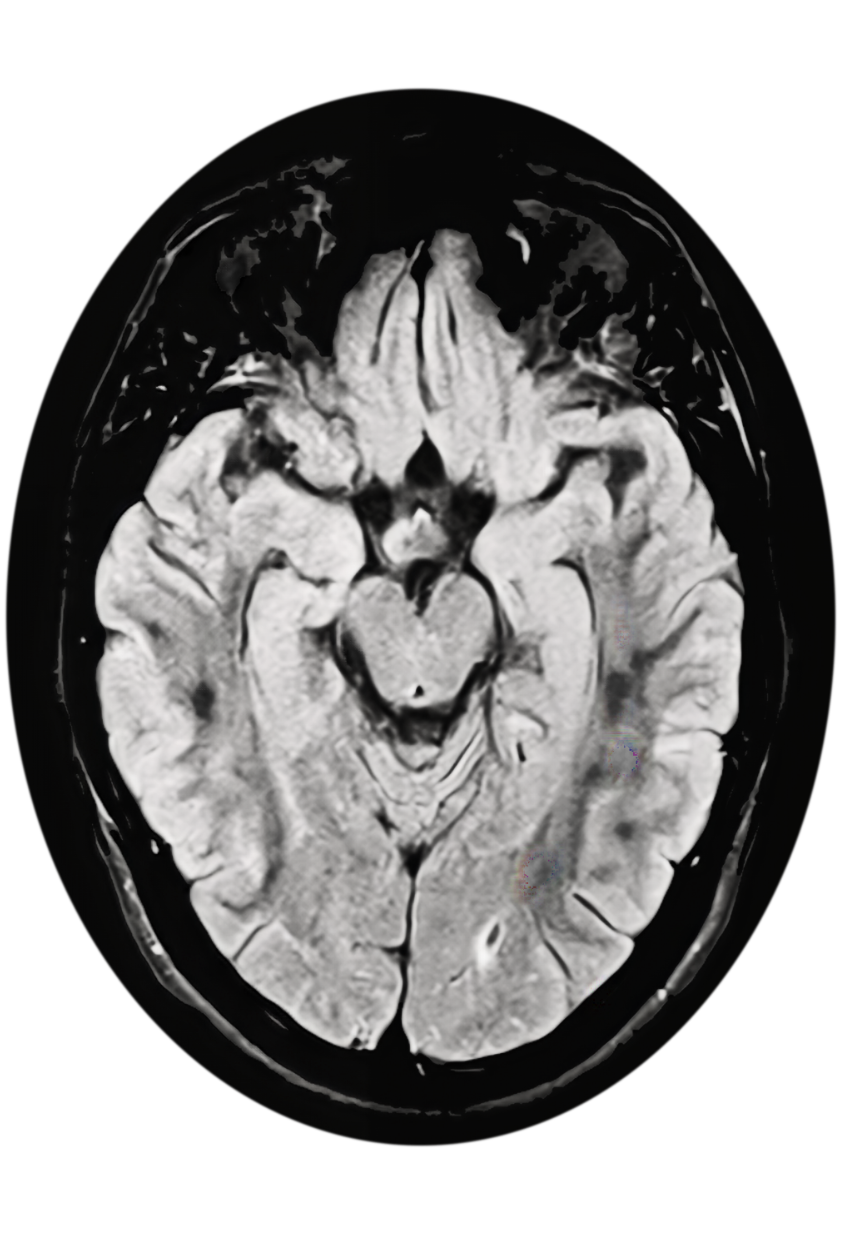

When a leukodystrophy or Alexander disease is suspected, prompt referral to a neurologist for a brain MRI and genetic testing is critical for timely diagnosis.10-13 Neuroimaging findings of frontally predominant white matter abnormalities, consistent with a leukodystrophy, are observed in those with earlier age of onset.1,15 In those with a later age of onset, neurodegenerative features with brainstem lesions and/or atrophy of the brainstem, cerebellum, and/or cervical spinal cord are typically observed.4,14,16